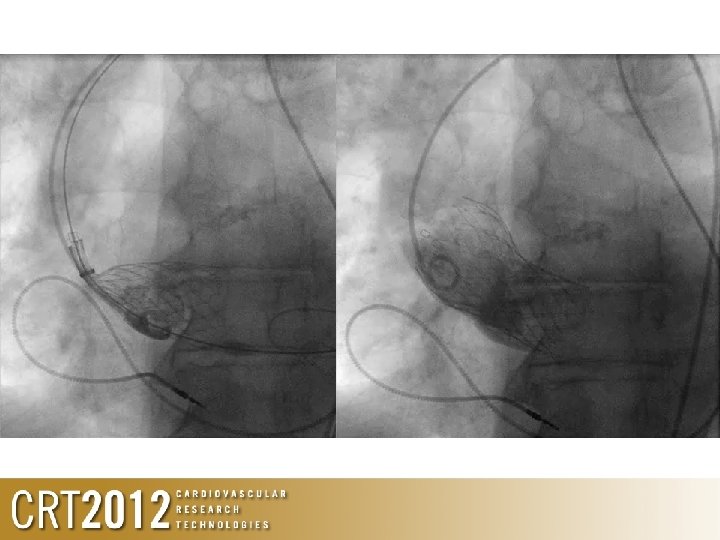

Valve too low

Valve too low • If the valve is so low that its affective MV, then, YOU WILL KNOW ABOUT IT – Significant angio leak – Significant haemodynamic change

What’s happening here?

Poor haemodynamics • Low diastolic pressure • No diacrotic notch • Haemodynamics worsening with time